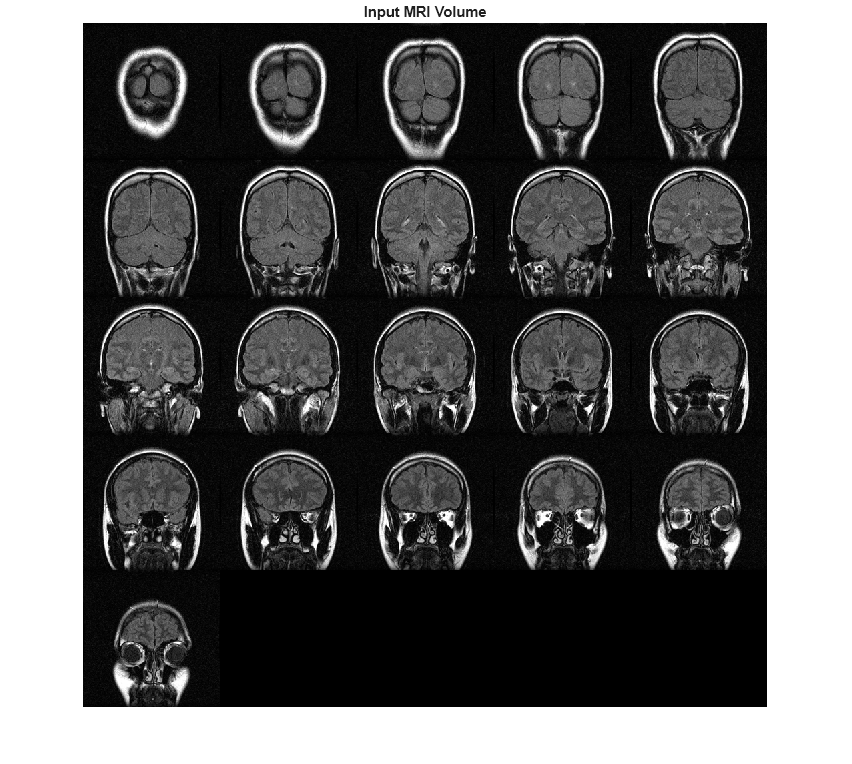

You can use data augmentation to increase the variety and quantity of training

data in deep learning applications, especially when available training data is limited, as is

typical in medical imaging. Data augmentation can be intensity augmentation, geometric

augmentation, or color augmentation. The jitterIntensity function performs

intensity augmentation of grayscale images and intensity volumes by randomly augmenting their

brightness, contrast, and gamma correction.